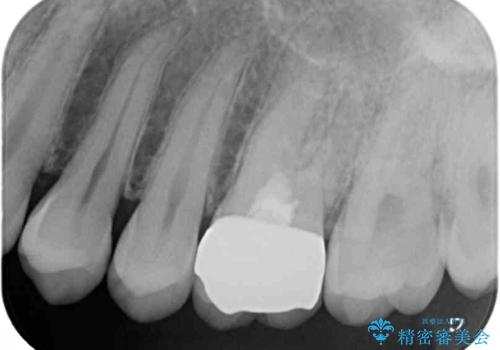

診査をしたところ、レントゲン写真よりとても大きなむし歯があることが分かりました。

虫歯が歯髄腔(神経の部屋)に達している可能性が非常に高かったため、炎症を起こしている神経組織を部分的に切除し、歯根部分の神経組織を保存する治療法が望ましいと考えられました。

処置開始前から神経組織を部分的に除去する可能性が高いことが分かっていたため、ラバーダムなどの環境を整え、無菌的環境下にて処置を進めて行きました。

虫歯は深くまで進行しており、歯冠部の神経から出血が認められました。神経を部分的に除去したところ出血が治まったので、生体親和性の非常に高いセメントにて充填し、仮封をしました。

後日状態を確認したところ、残された神経に異常がなかったため、セラミッククラウンにて補綴治療を行いました。